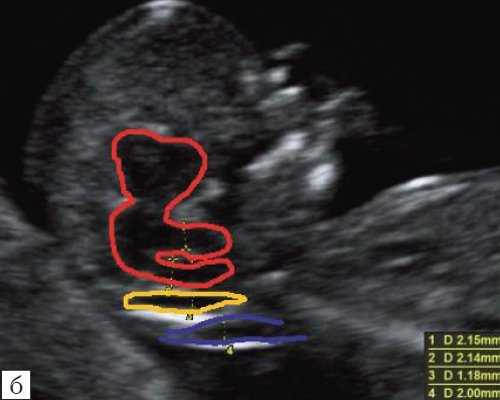

Новый ультразвуковой маркер в изучении нормальной ультразвуковой анатомии головного мозга плода в срок 11-14 недель беременности

Особенности визуализации изложенных выше структур в данном сроке позволили нам выделить и назвать новый ультразвуковой маркер нормальной ультразвуковой анатомии мозга плода. Структуры головного мозга плода в этой области схожи с осьминогом, у которого есть голова и две приблизительно равновеликие по диаметру ножки, представляющие собой ствол мозга и IV желудочек. Ниже ножек "осьминожки" визуализируется 2 "подушки осьминожки" - это два анэхогенных пространства - большая цистерна и воротниковое пространство (рис. 2, б).

Так как речь идет о сроках первого скрининга, т.е. раннего осмотра, новый ультразвуковой маркер мы назвали "осьминожкой" (рис. 3).

а) Стрелками указана голова "осьминожки" - диэнцефалон (таламус).

б) Красный цвет - диэнцефалон (таламус), со стволом мозга (верхняя ножка) и IV желудочком (нижняя ножка); желтый цвет - большая цистерна головного мозга; синий цвет - воротниковое пространство.

Как сказано выше, имеет значение и измерение ножек "осьминожки", так среднее значение диаметра нижней ножки, т.е. IV желудочка в зависимости от КТР в срок 11-14 недель варьирует от 1,5 до 2,5 мм (рис. 4).

Рис. 4. Измерение и взаимоотношение ножек "осьминожки" - ствола мозга и IV желудочка у плода, беременность 12 недель.

Измерение ножек "осьминожки".

Красный цвет - диэнцефалон (таламус), со стволом мозга (верхняя ножка) и IV желудочком (нижняя ножка); желтый цвет - большая цистерна головного мозга; синий цвет - воротниковое пространство.